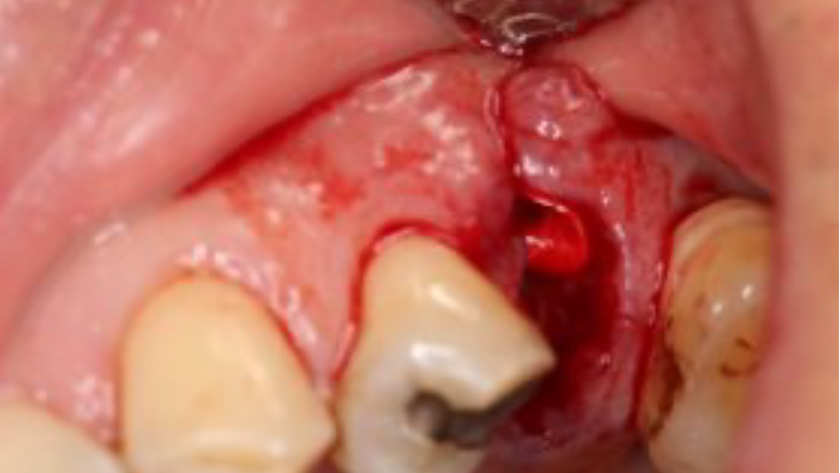

Tooth 13* required extraction in a 54-year-old male patient. The buccal bone was absent. Goal was to restore the site with an implant.